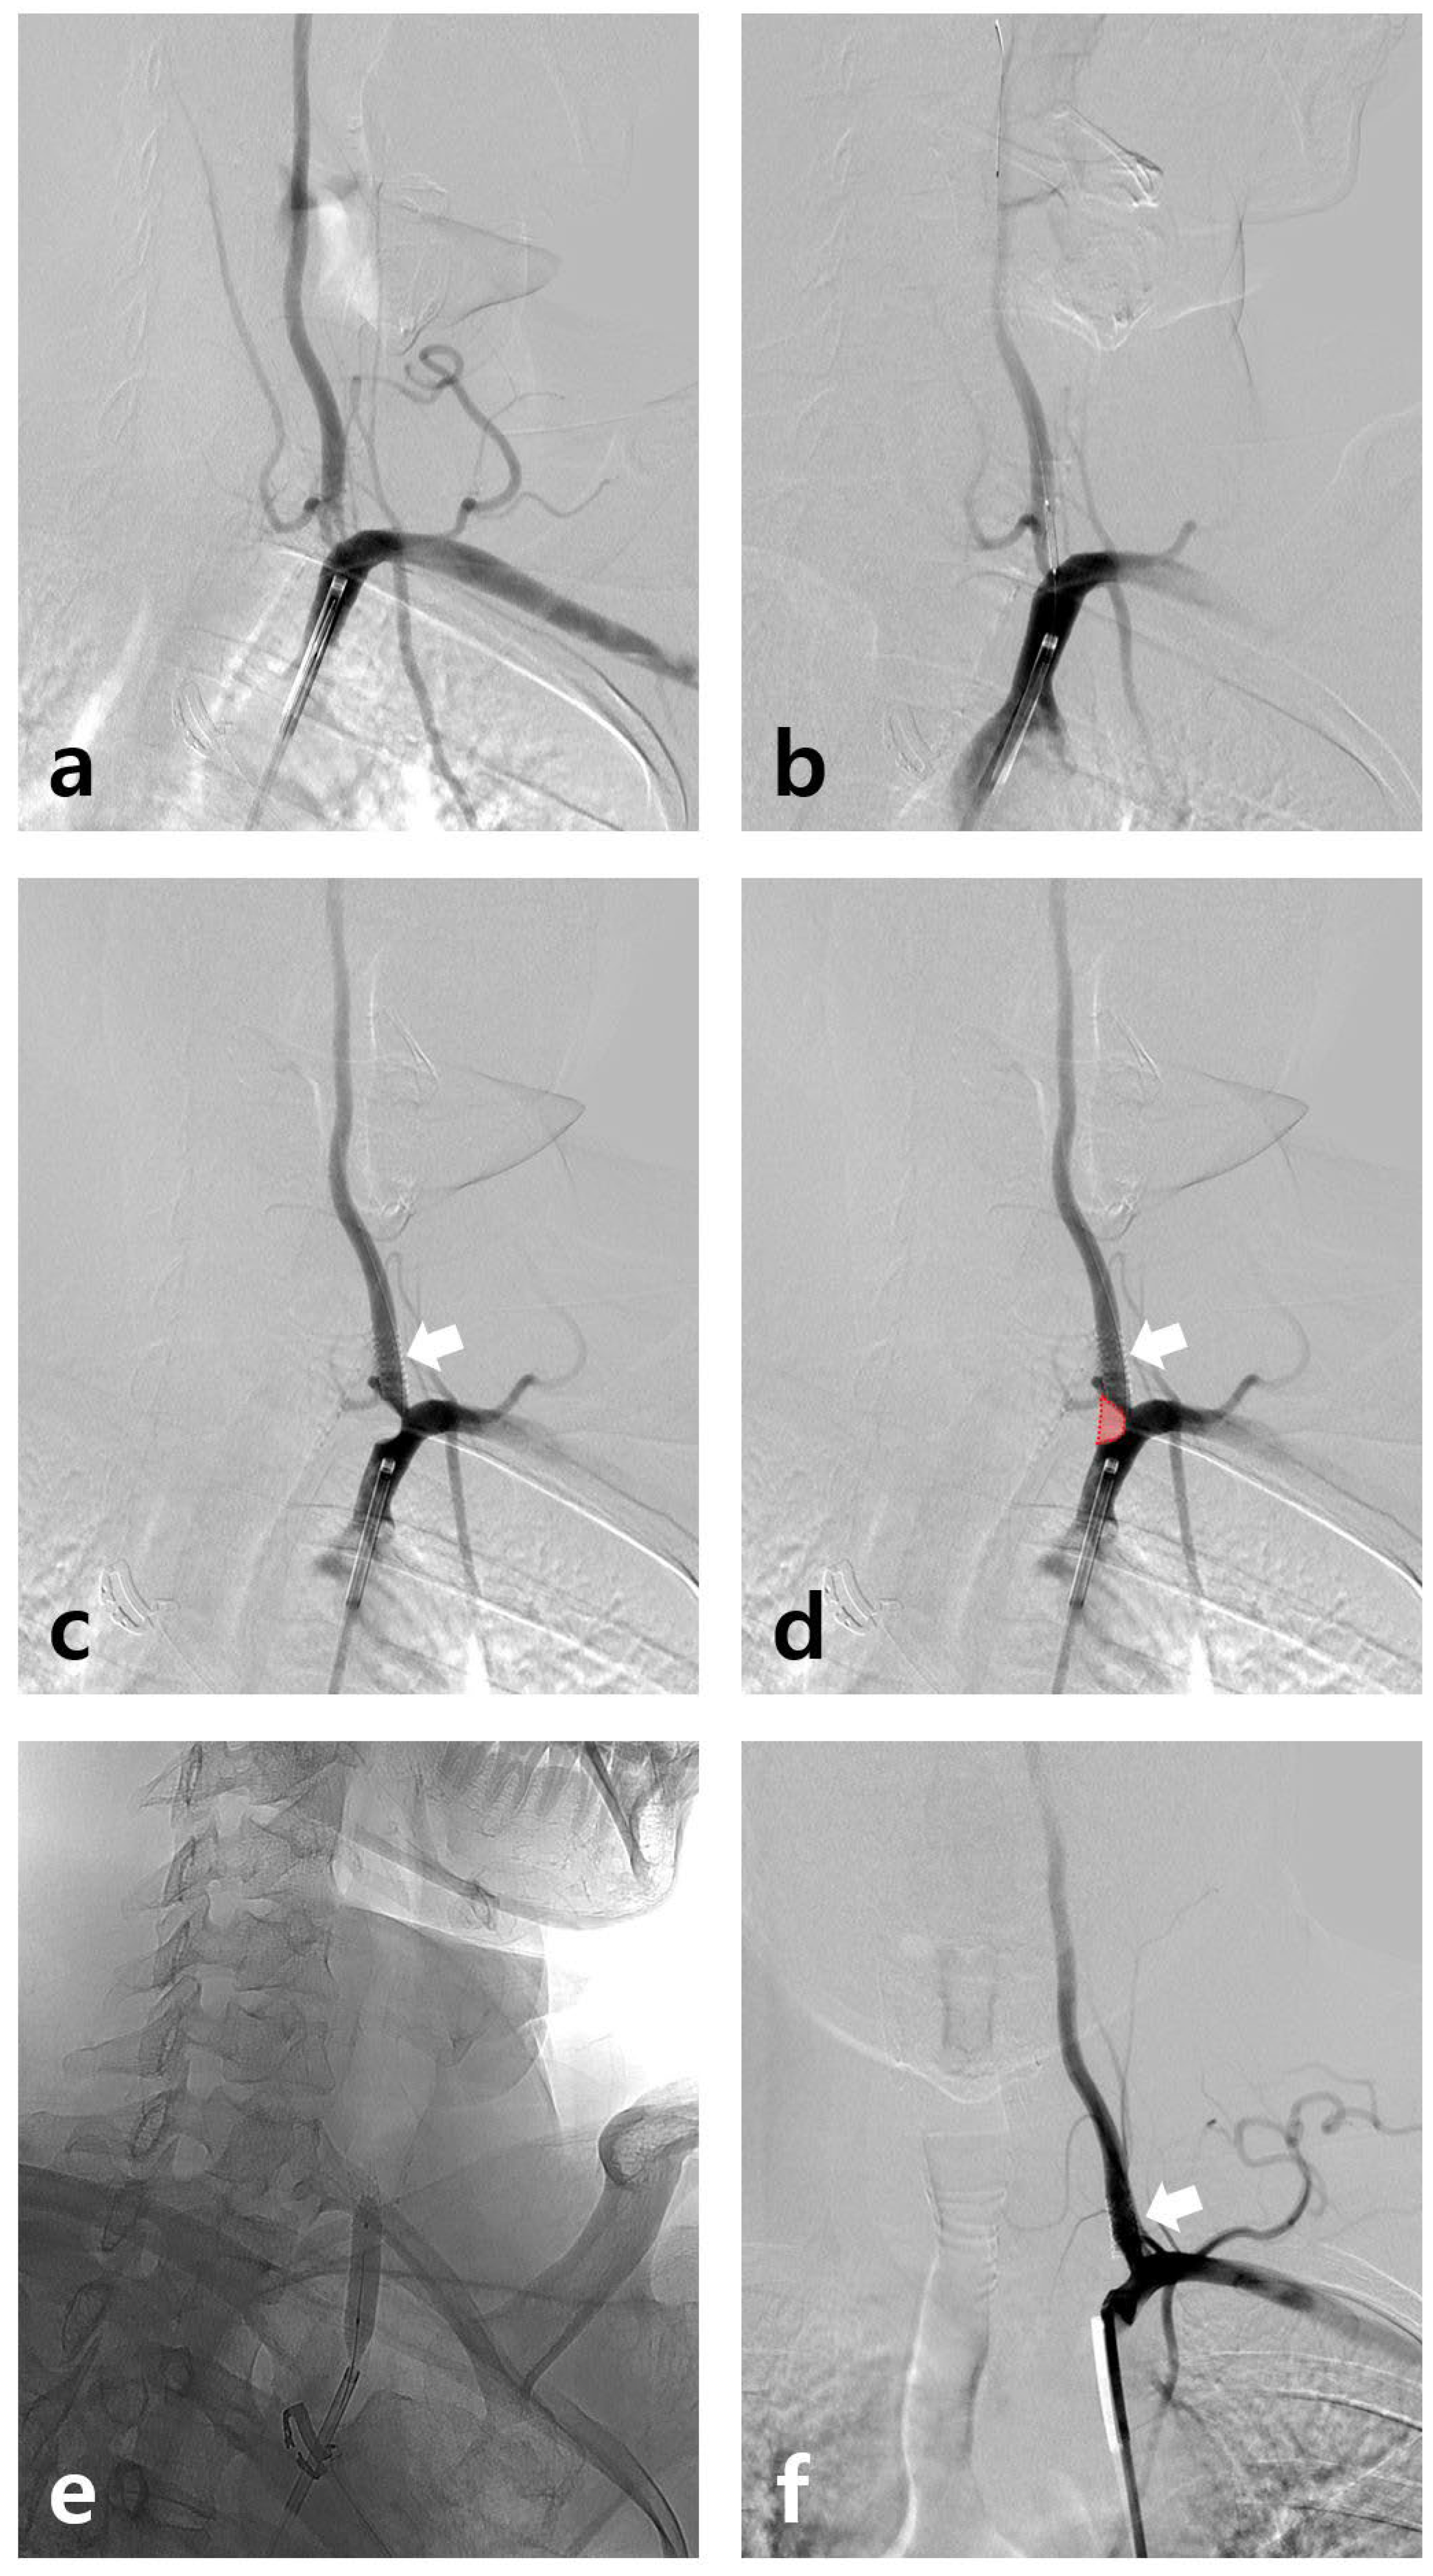

A 45-year-old male had suffered intermittent compressive left occipital headache radiating from the left shoulder for 5 years (10–15 days per month). His headache had worsened for a month (7/10 on the Visual Analog Scale). Brain computed tomography angiography showed severe stenosis at the orifice of the left vertebral artery (VA). A stent was inserted and the location of the balloon-mounted stent (Biotronik, Pro-kinteic Energy 5.0 × 13 mm) was confirmed under fluoroscopic guidance (Figure 1a,b). Due to the atheroma of the VA ostium, the balloon-mounted stent (arrow) distally migrated during inflation because of the hardening plaque (Figure 1c,d). It can be observed that the atheroma moved down from the VA origin as a result (Red block). An expansion of the narrowed left VA orifice (balloon angioplasty using Submarine 6–20) was confirmed, and the stent was positioned properly and VA flow improved (Figure 1e,f). His headache improved in a few days without recurrence during the one-year follow-up. Vertebrobasilar insufficiency can cause headaches, although the mechanism is not understood. Bow hunter’s syndrome, which occurs due to the rotational compression of the VA, accompanies headaches in approximately 7–9% of cases [1,2]. Few reports also showed that headache often occurs in lateral medullary ischemia due to an atherothrombotic cause (52–73%) [3,4]. The chronic headache, reported and attributed to vertebrobasilar insufficiency in this study, rapidly improved after stent insertion for the left VA severe stenosis.

Figure 1. (a) Stenosis from the left VA ostium confirmed on subclavian artery angiography. (b) The location of the balloon-mounted stent (Biotronik, Pro-kinteic Energy 5.0 × 13 mm) confirmed under fluoroscopic guidance. (c,d) Due to the atheroma of the VA ostium, the balloon-mounted stent (arrow) distally migrated during inflation. It can be observed that the atheroma moved down from the VA origin as a result (red block). (e) Additional balloon angioplasty using Submarine 6–20 was conducted in the ostium. (f) The stent is well-maintained (arrow) and VA flow improved.